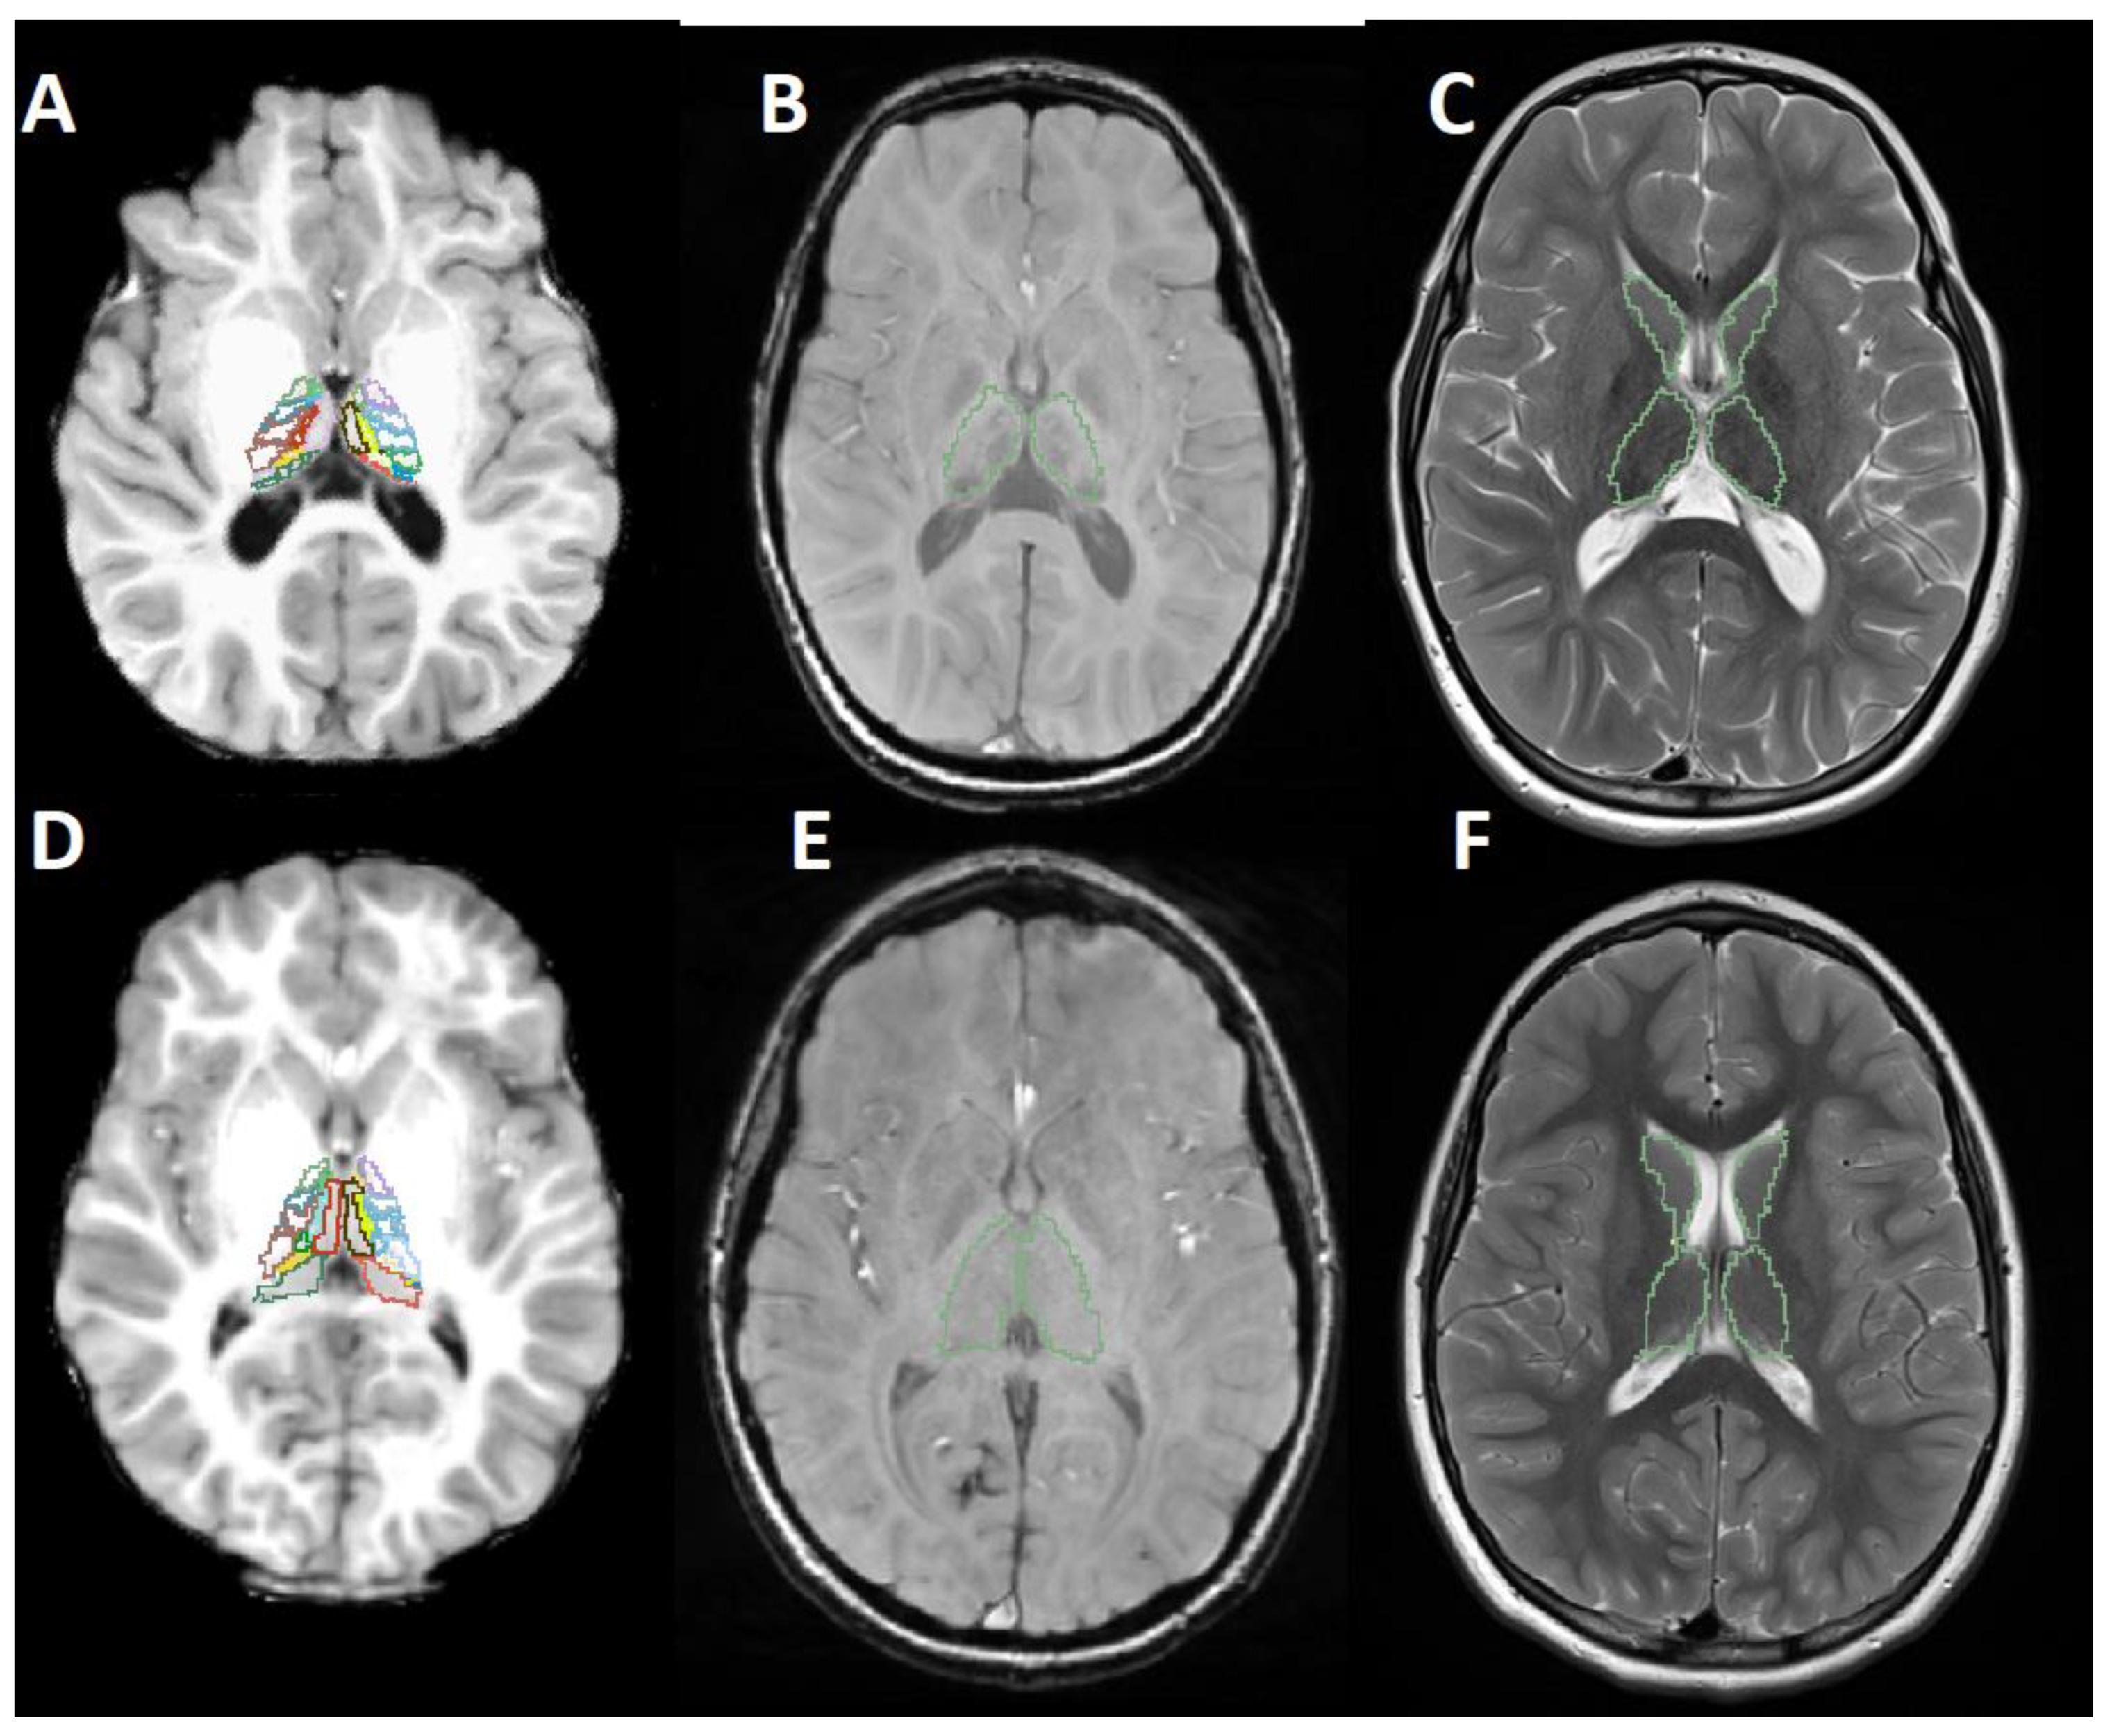

Figure 1 shows example data and the segmentation masks used to extract the classification features.

Figure 1.

MR images of an AGU patient (A–C) and an age- and sex-matched healthy control (D–F). (A,D) T1-weighted image with segmented thalamic nuclei. (B,E) Susceptibility weighted image with the outlines of the segmented thalamus. (C,F) T2-weighted image with the outlines of the segmented thalamus and the caudate.